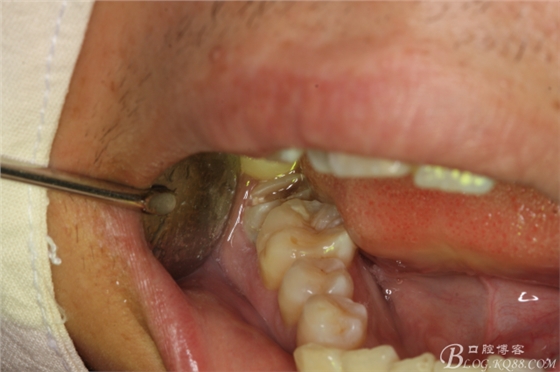

圖6.下牙槽神經(jīng)無(wú)痛阻滯麻醉

圖7.不切開(kāi)、不翻瓣、利用有限空間直接高速牙鉆分牙